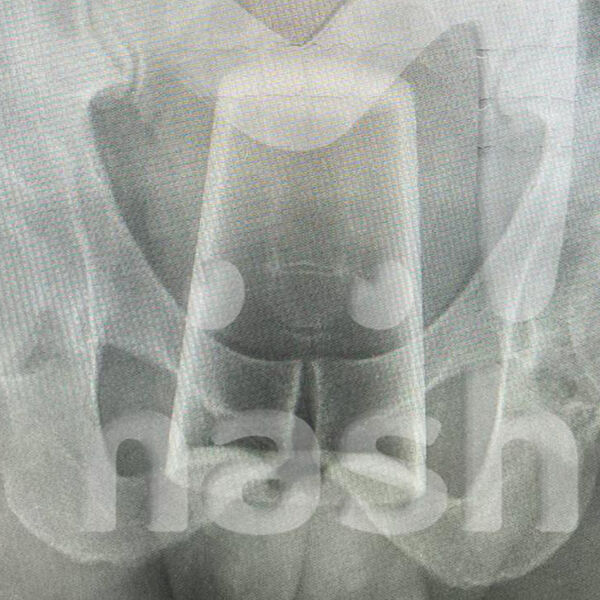

В Уфе мужчина попал в больницу со стаканом в заднем проходе после конкурса на 23 февраля. Об этом сообщает Telegram-канал Mash.

Инцидент произошел в День защитника Отечества, когда двое друзей отмечали праздник. По словам пострадавшего, они с товарищем выпили, закусили и решили устроить конкурс. Однако в какой-то момент он поскользнулся и нечаянно упал на стакан, после чего тот оказался у него в заднем проходе.

Попытки самостоятельно вытащить инородное тело не увенчались успехом — пострадавшему вызвали медиков. Позже врачи извлекли стакан из заднего прохода мужчины и отпустили его домой, порекомендовав регулярно наблюдаться у специалистов после случившегося.